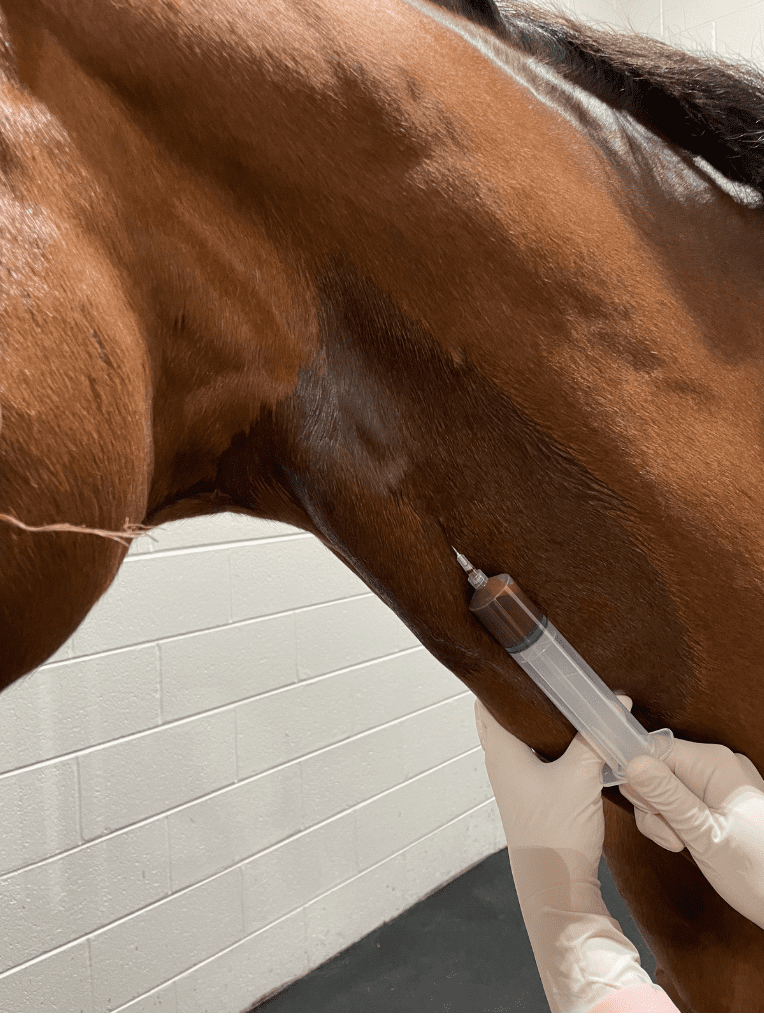

Using Regenerative Medicine to Improve Healing in Soft Tissue Injuries

Equine athletes of all disciplines are prone to soft tissue injuries. Common injuries include superficial digital flexor (SDF) tendonitis, deep digital flexor (DDF) tendonitis, suspensory ligament desmitis, collateral ligament desmitis, and meniscal tears and degeneration. Unfortunately, soft tissues including tendons, ligaments, and menisci, have limited intrinsic healing capabilities. Resultant repair tissue is often biomechanically inferior...